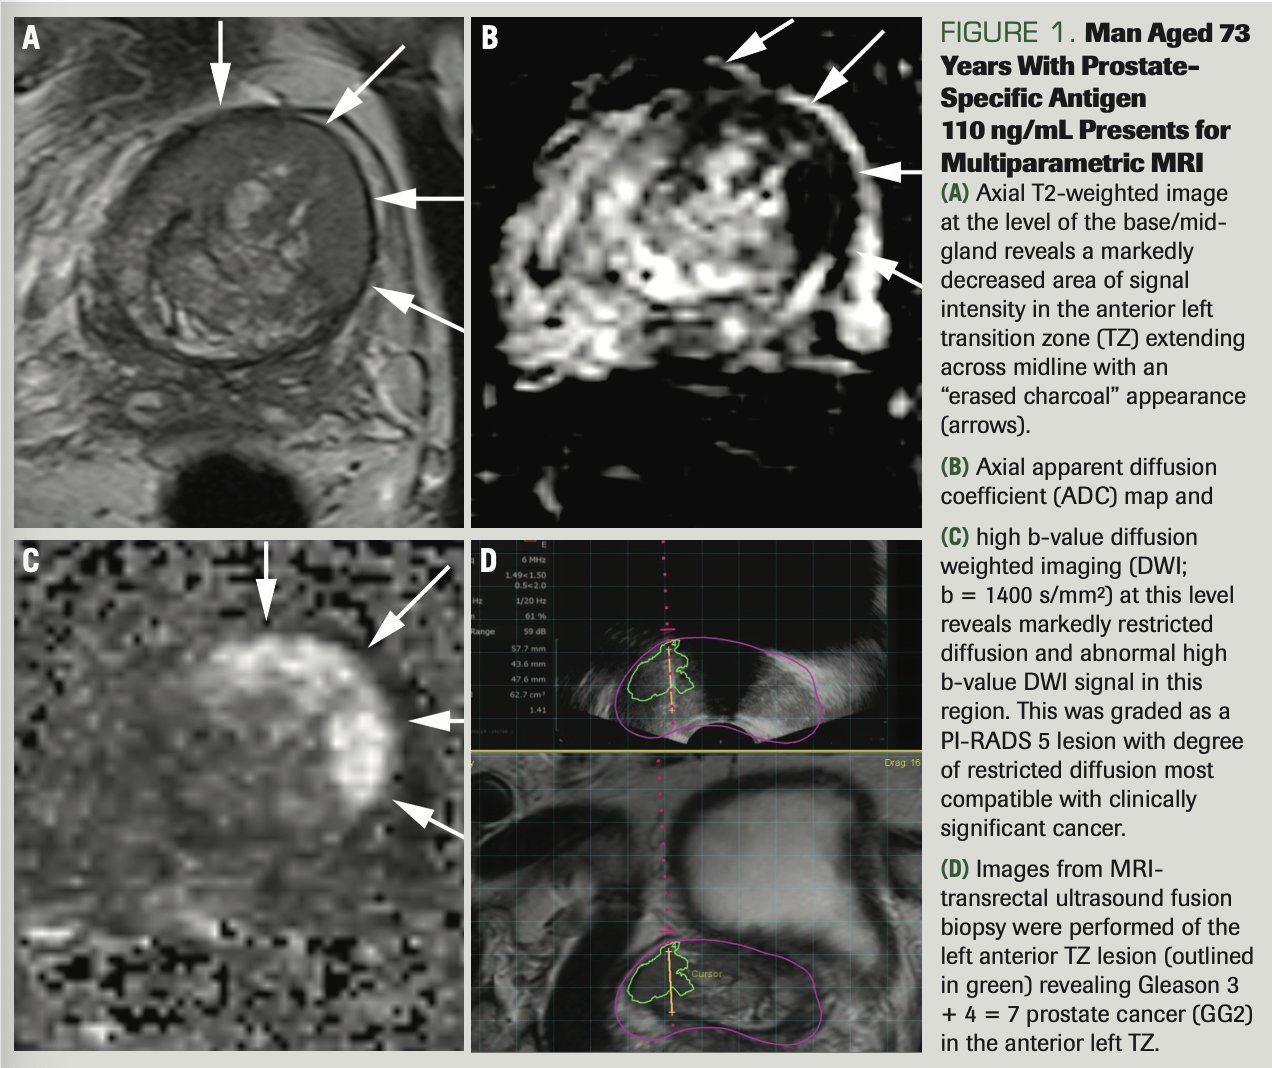

A PI-RADS 5 lesion was identified in the left anterior TZ (Figures 1A-1D), and an 18-core TRUS fusion biopsy shortly thereafter revealed 2 cores of Gleason 3 + 4 = 7, Gleason grade (GG) 2 disease (Figure 2A). After metastatic staging with a negative CT and nuclear medicine bone scan, he underwent open radical prostatectomy (RP) in May 2021. Final pathology revealed a 66-gram prostate, Gleason 4 + 3 = 7, GG3, organ-confined disease with negative lymph nodes, pT2N0Mx (Figure 2B).

FIGURE 1. Man Aged 73 Years With Prostate- Specific Antigen

110 ng/mL Presents for Multiparametric MRI

(A) Axial T2-weighted image at the level of the base/mid- gland reveals a markedly decreased area of signal intensity in the anterior left transition zone (TZ) extending across midline with an “erased charcoal” appearance (arrows).

(B) Axial apparent diffusion coefficient (ADC) map and

(C) high b-value diffusion weighted imaging (DWI;

b = 1400 s/mm2) at this level reveals markedly restricted diffusion and abnormal high b-value DWI signal in this region. This was graded as a PI-RADS 5 lesion with degree of restricted diffusion most compatible with clinically significant cancer.

(D) Images from MRI- transrectal ultrasound fusion biopsy were performed of the left anterior TZ lesion (outlined in green) revealing Gleason 3 + 4 = 7 prostate cancer (GG2) in the anterior left TZ.

A: Prostate MRI is a challenging imaging study to interpret, especially in the TZ. The TZ is challenging because of the overlap in imaging appearance of certain types of benign prostatic hyperplasia nodules with malignancy. Specifically, the degree of restricted diffusion and contrast enhancement can overlap with stromal and hyperplastic nodules, respectively. That said, there are morphologic features of anterior TZ lesions that are critical to recognize. Specifically, T2 weighted imaging is the dominant imaging sequence used to diagnose and characterize TZ lesions and these are characterized by an “erased charcoal” appearance, as in this case. Also, these lesions should have markedly restricted diffusion as evidenced by low signal on apparent diffusion coefficient (ADC) maps and high signal on high b-value diffusion weighted imaging (DWI).